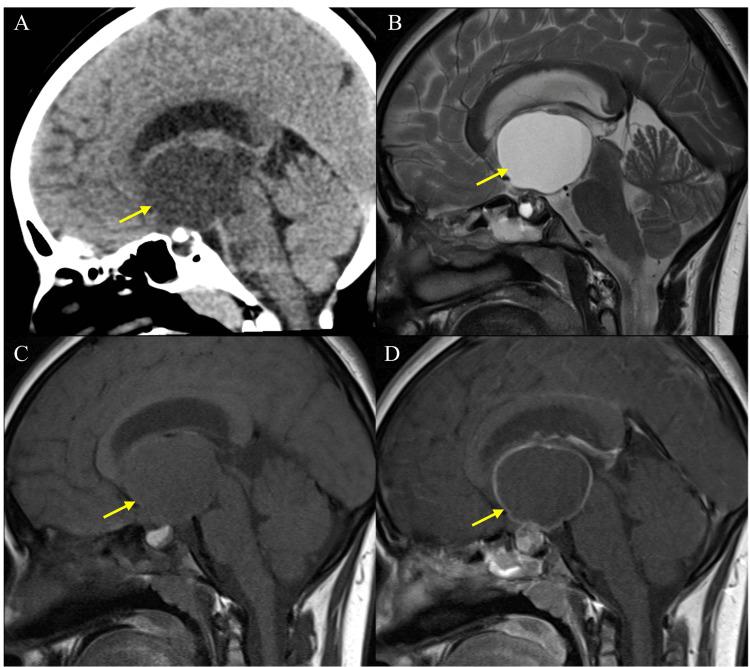

颅内囊肿:单机构27例手术治疗经验

Introduction Intracranial cysts (ICs) are rare pathologies that are often found incidentally during radiological examinations. They may appear in various brain regions and are categorized as normal, congenital, traumatic, or tumor-associated variants. ICs can be asymptomatic or cause symptoms, such as headaches, visual impairments, or seizures, depending on their size and location. Severe complications include obstructive hydrocephalus, loss of consciousness, and intracranial bleeding. Surgical excision is the most accepted type of management in most ICs. Objectives This study aimed to evaluate 27 surgically managed ICs in a tertiary hospital focusing on their clinical, radiological, histopathological, surgical outcomes, and prognosis to enhance understanding and management of these rare, benign cysts. Methodology This retrospective cohort study included 27 surgically managed ICs with pathological confirmation in King Abdulaziz Medical City, National Guard Health Affairs, Jeddah, Saudi Arabia, from May 2016 to May 2023. All extracranial and nonsurgically managed cysts have been excluded from this study. Data on demographics, clinical presentations, radiological features, surgical outcomes, and follow-up were retrospectively extracted and analyzed. MRI and CT scans were reviewed to determine cyst characteristics. Surgical outcomes and postoperative complications were recorded. Data were collected via Google Forms and analyzed using the JMP Pro software. Ethical approval was obtained from King Abdullah International Medical Research Center, Jeddah, Saudi Arabia. Results The study included 27 ICs: 11 (40.74%) colloid cysts, six (22.22%) epidermoid cysts, five (18.51%) adamantinomatous craniopharyngiomas, two (7.40%) neuroepithelial cysts, and one each of Rathke's cleft cyst (3.70%), xanthogranuloma (3.70%), and dermoid cyst (3.70%). All 27 cases were surgically managed (100.00%), with gross total resection achieved in 14 (51.85%) cases. Only 12 cases (44.44%) did not develop any surgical complications. Twenty-two cases (81.48%) experienced an improvement in the preoperative presenting symptoms. During the follow-up, only three cases (11.11%) had evidence of recurrence. Conclusion This study analyzed 27 ICs of various histopathological types. Each type showed distinct clinical and radiological features. Surgical management generally improved preoperative symptoms with low mortality and recurrence rates, although complications were common. Identifying specific radiological features is crucial for an accurate preoperative diagnosis and optimal surgical outcomes.

结果

该研究纳入27例颅内囊肿:11例(40.74%)为胶样囊肿,6例(22.22%)为表皮样囊肿,5例(18.51%)为造釉细胞瘤型颅咽管瘤,2例(7.40%)为神经上皮囊肿,拉克囊囊肿、黄色肉芽肿及皮样囊肿各1例(各占3.70%)。所有27例均接受了手术治疗(100.00%),14例(51.85%)实现了全切。仅12例(44.44%)未发生任何手术并发症。22例(81.48%)术前出现的症状有所改善。随访期间,仅有3例(11.11%)有复发迹象。

结论

本研究分析了27例不同组织病理学类型的颅内囊肿。每种类型均表现出独特的临床和影像学特征。手术治疗通常可改善术前症状,死亡率和复发率较低,尽管并发症很常见。识别特定的影像学特征对于准确的术前诊断和最佳手术结果至关重要。